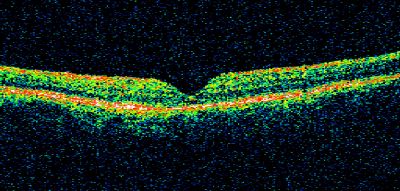

Macular Hole Closed with Vitrectomy - Post-op 20/60 Vision

Macular Hole

closed

vitrectomy